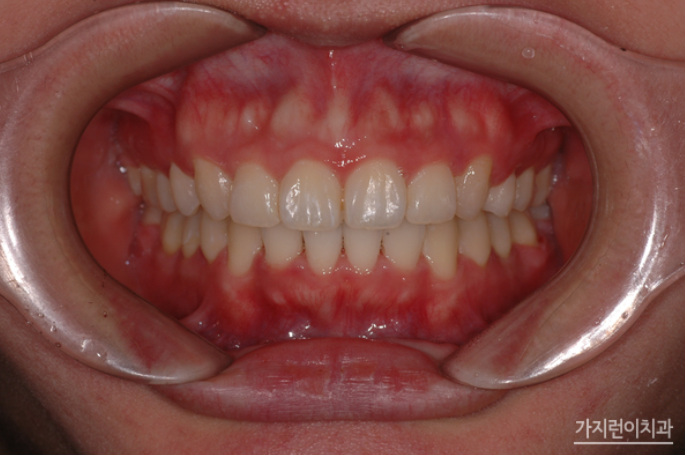

사랑니 세우는 교정 전후

송곳니의 덧니 증상과 더불어 돌출입, 비뚠 치아배열 등 여러 문제가 많은 구강이었는데 어떤가요? 덧니의 흔적을 찾기 어려울 정도로 가지런하게 개선된 것을 확인할 수 있었는데요. 상악의 돌출감도 해소되었고 어금니 3개를 발치하게 되었는데도 티가 나지 않는 다는 걸 확인할 수 있었습니다. 그만큼 사랑니가 감쪽같이 어금니의 외형과 역할을 대신하게 된 것인데요. 충치로 치아를 발치해야 한다면 임플란트만 고집하지 마시고 본인의 구강상태에 따라 사랑니를 바로 세워 치아교정으로 임플란트 대신 치아기능을 회복해볼 수 있다는 것을 확인해볼 수 있는 사례였습니다.